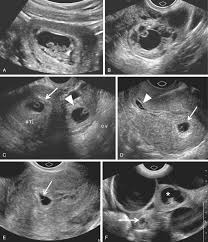

These cul-de-sacs are important because they can hold fluid. During an ultrasound, your doctor might look for fluid in these cul-de-sacs. This could be a sign of several things, like:

Pelvic inflammatory disease (PID): An infection in the reproductive organs.

Endometriosis: A condition where tissue that’s normally found inside the uterus grows outside of it.

Ovarian cysts: Fluid-filled sacs that form on the ovaries.

Ectopic pregnancy: A pregnancy that occurs outside of the uterus.

Other conditions: There are other reasons why fluid might build up in the cul-de-sacs, so it’s important to talk to your doctor about any concerns you have.

Pelvic Inflammatory Disease (PID): PID is an infection of the reproductive organs. It can cause inflammation and swelling, leading to fluid buildup in the cul-de-sac.

Ectopic Pregnancy: An ectopic pregnancy is when a fertilized egg implants outside the uterus, often in the fallopian tube. If the pregnancy ruptures, it can cause bleeding and fluid in the cul-de-sac.